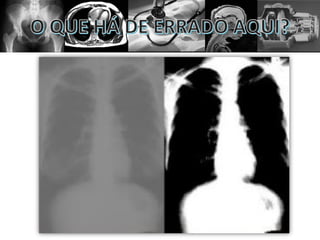

• O contraste é a diferenciação dos tecidos;

• O contraste é a absorção diferencial.

Contraste alto ou baixo não significam ser bom

ou ruim por si só. Diferentes estruturas precisam

de determinado tipo de contraste específico.